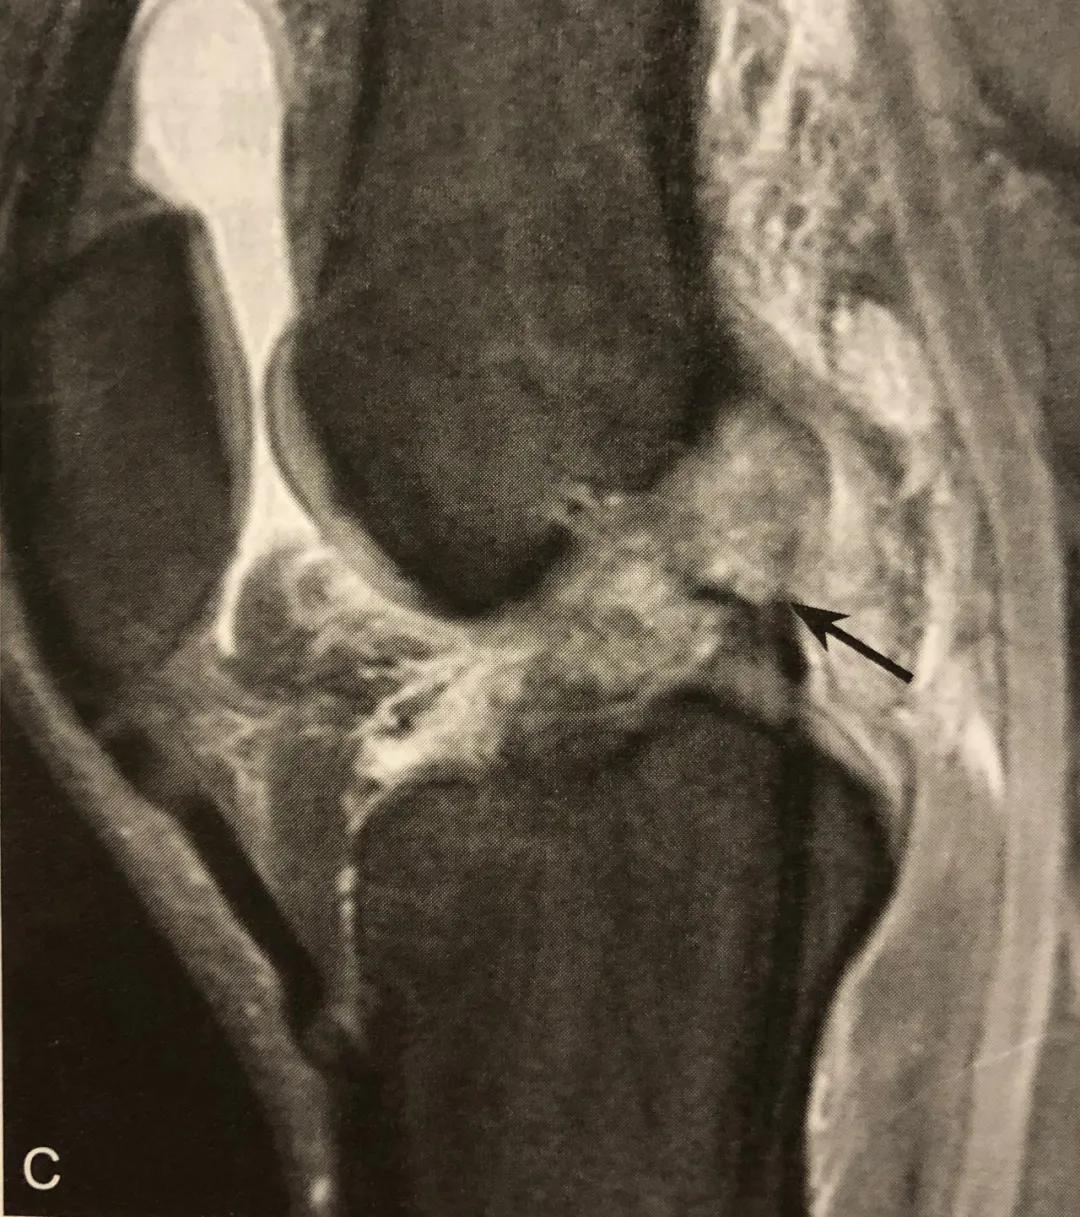

侧囊征/ Segond 骨折

A. 膝关节 ⅹ 线前后位片,胫骨平台外侧缘撕脱椭圆形小碎骨片,长轴平行于胫骨,见侧囊征;

B. 同一患者 MRI 冠状位 PDWI SPAIR 显示胫骨平台外侧缘撕脱骨折,内外侧半月板内横形高信号,提示损伤(粗箭头);

C. 矢状位 PDWI SPAIR 中间层面 PCL 显示肿胀,信号不均,提示 PCL 水肿,呈轻度损伤

侧囊征在膝关节 x 线前后位或 CT、MRI 冠状位显示,表现为胫骨平台外侧缘撕脱椭圆形小碎骨片,长轴平行于胫骨。

CT 可显示多数碎骨片向外移位,股骨内外侧髁和胫骨后缘骨折;MRI 可观察膝关节韧带和半月板损伤情况,韧带和半月板可呈轻度水肿、部分撕裂和完全撕裂,T2WI 信号增高,关节面下常见骨挫伤表现。

阅片要点:

1. 在膝关节 Ⅹ 线前后位片或 CT、MRI 冠状位观察;

2. X 线片或 CT 观察到侧囊征( Segond骨折),应该建议 MRI 检查;

3. Segond 骨折是 PF-ITB 和 ALL 胫骨附着点撕脱骨折的直接征象;

4. Segond 骨折和 ACL 断裂具有高度相关性,但无直接关系;

5. 无 ACL 损伤的 Segond 骨折,MRI 需注意观察其他韧带、半月板及骨质损伤;

6. MRI 注意观察伴发的关节面下对吻性骨挫伤表现。